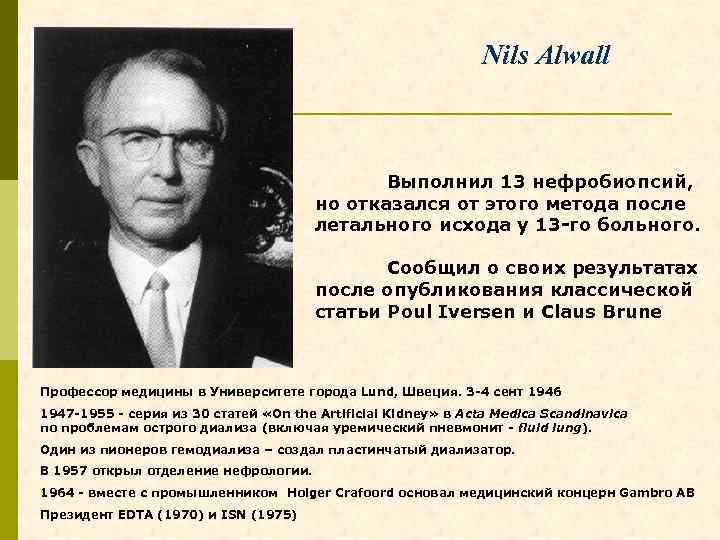

Nils Alwall Выполнил 13 нефробиопсий, но отказался от этого метода после летального исхода у 13 -го больного. Сообщил о своих результатах после опубликования классической статьи Poul Iversen и Claus Brune Профессор медицины в Университете города Lund, Швеция. 3 -4 сент 1946 1947 -1955 - серия из 30 статей «On the Artificial Kidney» в Acta Medica Scandinavica по проблемам острого диализа (включая уремический пневмонит - fluid lung). Один из пионеров гемодиализа – создал пластинчатый диализатор. В 1957 открыл отделение нефрологии. 1964 - вместе с промышленником Holger Crafoord основал медицинский концерн Gambro AB Президент EDTA (1970) и ISN (1975)

Nils Alwall Профессор медицины в Университете города Lund, Швеция. 1947 -1955 - серия из 30 статей «On the Artificial Kidney» в Acta Medica Scandinavica по проблемам острого диализа (включая уремический пневмонит - fluid lung). В 1957 образовал отделение нефрологии. Один из пионеров гемодиализа. сконструировал пластинчатый диализатор. Вместе с промышленником Holger Crafoord в 1964 г. основал шведский медицинский концерн Gambro AB Президент EDTA (1970) и ISN (1975)